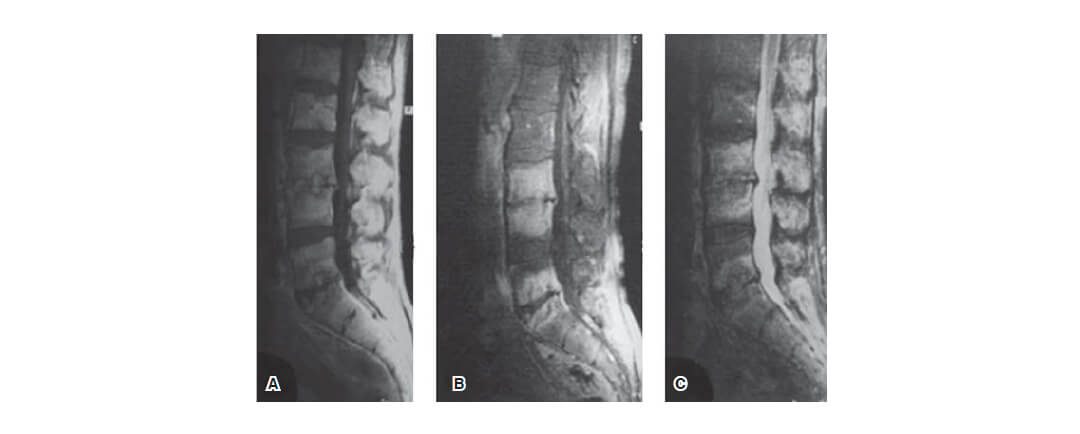

por Dr. Esteban Castro | Feb 6, 2020 | Columna

MAL DE POTT (TUBERCULOSIS VERTEBRAL)IntroducciónFactores de RiesgoClínicaDiagnósticoTratamiento MAL DE POTT (TUBERCULOSIS VERTEBRAL) Mal de Pott Introducción La tuberculosis de la columna vertebral, también conocida como mal de Pott, es una enfermedad crónica y...